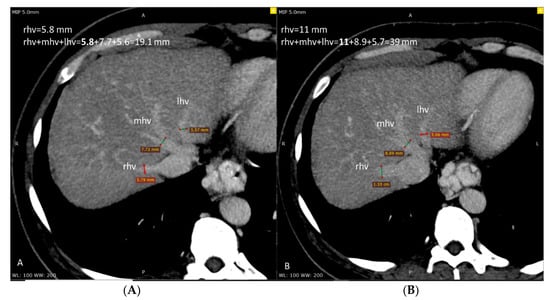

3.2. Hepatic Veins Diameters

| Right hepatic vein diameter (mm) | 6.36 | 3.94 | 8.12 | 4.20 | <0.001 |

| Middle hepatic vein diameter (mm) | 5.70 | 2.48 | 5.91 | 2.51 | ns |

| Left hepatic vein diameter (mm) | 6.69 | 3.17 | 6.65 | 3.19 | ns |

| Sum of hepatic vein diameters (mm) | 19.29 | 9.52 | 21.44 | 9.06 | 0.028 |